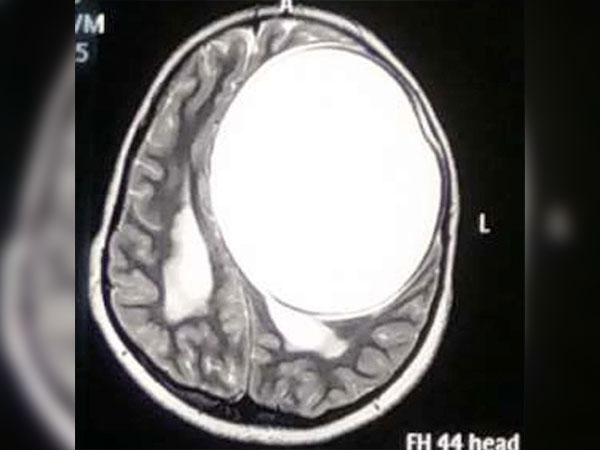

ನರರೋಗ ತಜ್ಞರು ಆಕೆಯನ್ನು ಪರೀಕ್ಷಿಸಿ ಎಂಆರ್ ಐ ಸ್ಕ್ಯಾನ್ ಮಾಡಿದ ಬಳಿಕ ಬಾಲಕಿಯ ತಲೆಯಲ್ಲಿ ಟೇಪ್ ವರ್ಮ್ ಕೋಶ ಇರುವುದು ಪತ್ತೆಯಾಗಿದೆ ಮತ್ತು ಇದು ಮೆದುಳಿನ ಅರ್ಧ ಭಾಗದಷ್ಟಿತ್ತು.

ನೀತಾಳ ತಲೆಯಲ್ಲಿ ಪತ್ತೆಯಾದ ಕೋಶ ಸುಮಾರು 675 ಗ್ರಾಂನಷ್ಟು ಭಾರವಿತ್ತು ಮತ್ತು 12.2 ಸೆ.ಮೀx11ಸೆ.ಮೀ.x9.8 ಸೆ.ಮೀ. ನಷ್ಟಿತ್ತು.